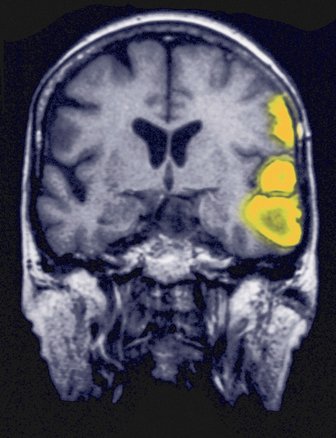

3. Ngủ quá ít gây ra những sai lầm trong quyết định lựa chọn thực phẩm

Các nhà nghiên cứu từ lâu đã biết rằng ngủ quá ít có thể dẫn đến tăng cân, nhưng trong 12 tháng qua, các nhà khoa học đã đạt được một bước tiến, tìm ra nguyên nhân của vấn đề này. Nghiên cứu cho thấy rằng: các khu vực của não bộ giúp chúng ta cân nhắc những yếu tố quyết định ăn một thực phẩm nào đó bị ảnh hưởng bởi việc ngủ quá ít. Ngủ quá ít gây khó khăn cho bộ não trong việc lựa chọn thực phẩm tốt cho sức khỏe. Một nghiên cứu khác theo dõi phản ứng hình ảnh của các loại thực phẩm lành mạnh và không lành mạnh cho thấy rằng vào những đêm mà người tham gia chỉ ngủ 4 tiếng, họ có xu hướng lựa chọn loại thực phẩm không lành mạnh và đưa ra quyết định sai lầm.